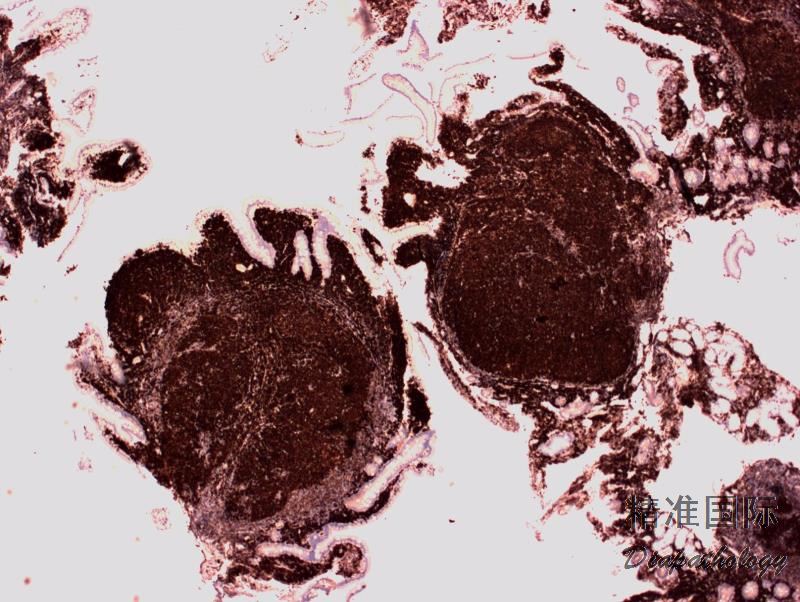

淋巴结正常结构消失,代之以紧密排例、大小和形状一致的不正常滤泡,常累及整个淋巴结或浸润到胞膜外。套区变薄、不完整、消失或极性不在。有的同时存在弥漫浸润区。偶而滤胞呈现出形状不规则或匐行性生长(类似进行性滤胞中心转化, PTGC)。

滤泡由中心细胞和不等数量的中心母细胞组成,两种细胞随机散在分布,极性和“星空”细胞消失。滤泡之间或可见浸润中心细胞。中心细胞:较中心母细胞小,核形不规则成角或有核裂,胞质少。中心母细胞:核圆形或卵圆形,呈空泡状,可见 1 ~ 3 核仁,多靠近核膜。滤泡之间或可见肿瘤细胞侵润,系中心细胞,但胞核相对规则。